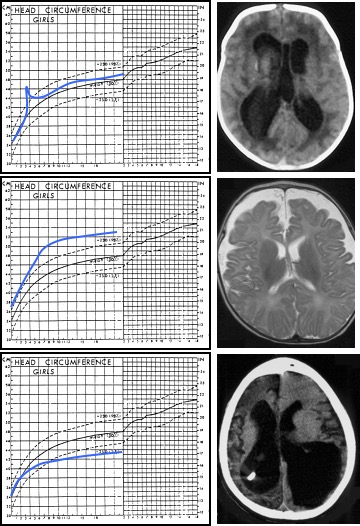

l’hydrocéphalie se manifeste par une hypertension intracrânienne, qui chez le nourrisson entraîne une augmentation du périmètre crânien ; la surveillance de sa croissance est donc un élément indispensable du suivi de tout nourrisson. Chez l’enfant plus grand, on rencontre un tableau d’hypertension intracrânienne d’évolution plus ou moins rapide. le diagnostic anténatal soulève la question du pronostic, qui est souvent réservé voire très défavorable.

on la diagnostique avant tout devant une augmentation du périmètre crânien, qu’il faut idéalement dépister précocement, au moment de la rupture de la courbe (et non quand les valeurs sont au dessus du 97ème percentile).

la sémiologie radiologique retrouve les éléments définissant l’hydrocéphalie : augmentation du volume du liquide et trouble de sa circulation :

le scanner

l’IRM

plus difficile à être en oeuvre car plus longue et nécessitant souvent une sédation, c’est elle qui étudie au mieux le tissu cérébral, pour donner des indications sur la cause de l’hydrocéphalie (traces de saignement en période périnatale) et son retentissement et son pronostic (analyse des leucopathies périventriculaires). elle permet également d’étudier le flux du LCS, en pré et en post-opératoire, ce qui oriente la décision chirurgicale.